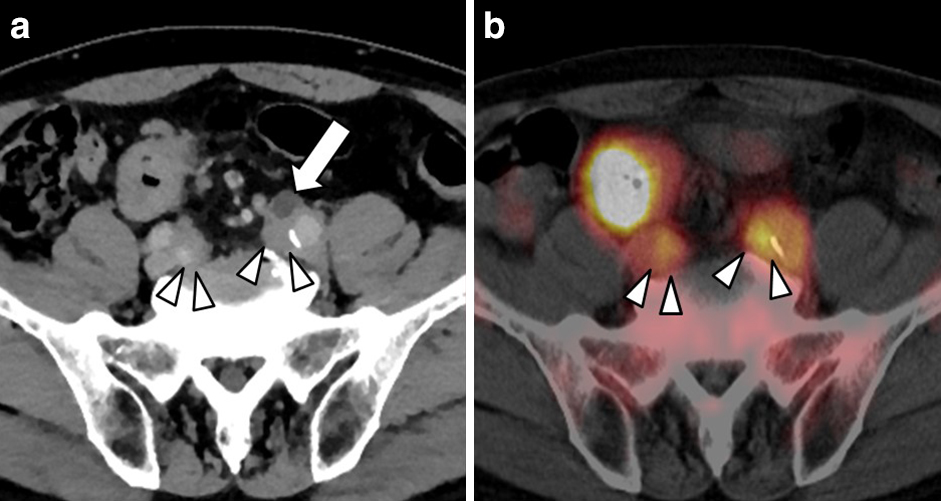

腹部造影CT所見:直腸S状部からS状結腸にかけて造影効果を伴う全周性の壁肥厚を認めた.腫瘍の壁外進展,リンパ節転移,遠隔転移の所見は認めなかった.また,両側総腸骨動脈,下腸間膜動脈根部近傍の腹部大動脈周囲に軟部陰影を認め(Fig. 2a矢頭),左総腸骨動脈周囲の軟部陰影により左尿管は狭窄し水腎症を来していた(Fig. 2a矢印).

a: Contrast-enhanced CT showed soft masses which were found bilaterally, peripheral to the common iliac arteries (arrowheads). Hydronephrosis of the left ureter was caused by the left soft mass (arrow). b: PET-CT showed increased FDG accumulation which was found at the rectosigmoid junction. Increased FDG accumulation was found at the bilateral soft masses peripheral to the common iliac arteries (arrowheads).

PET-CT所見:直腸癌にstandardized uptake value(以下,SUVと略記)max 13.3,左総腸骨動脈周囲軟部陰影にSUVmax 5.5,右総腸骨動脈周囲軟部陰影にSUVmax 4.2の18F-FDGの異常集積を認めた(Fig. 2b矢頭).腹部大動脈周囲の軟部陰影にもSUVmax 5.5の18F-FDGの異常集積を認めた(Fig. 3a矢頭,3b矢頭).